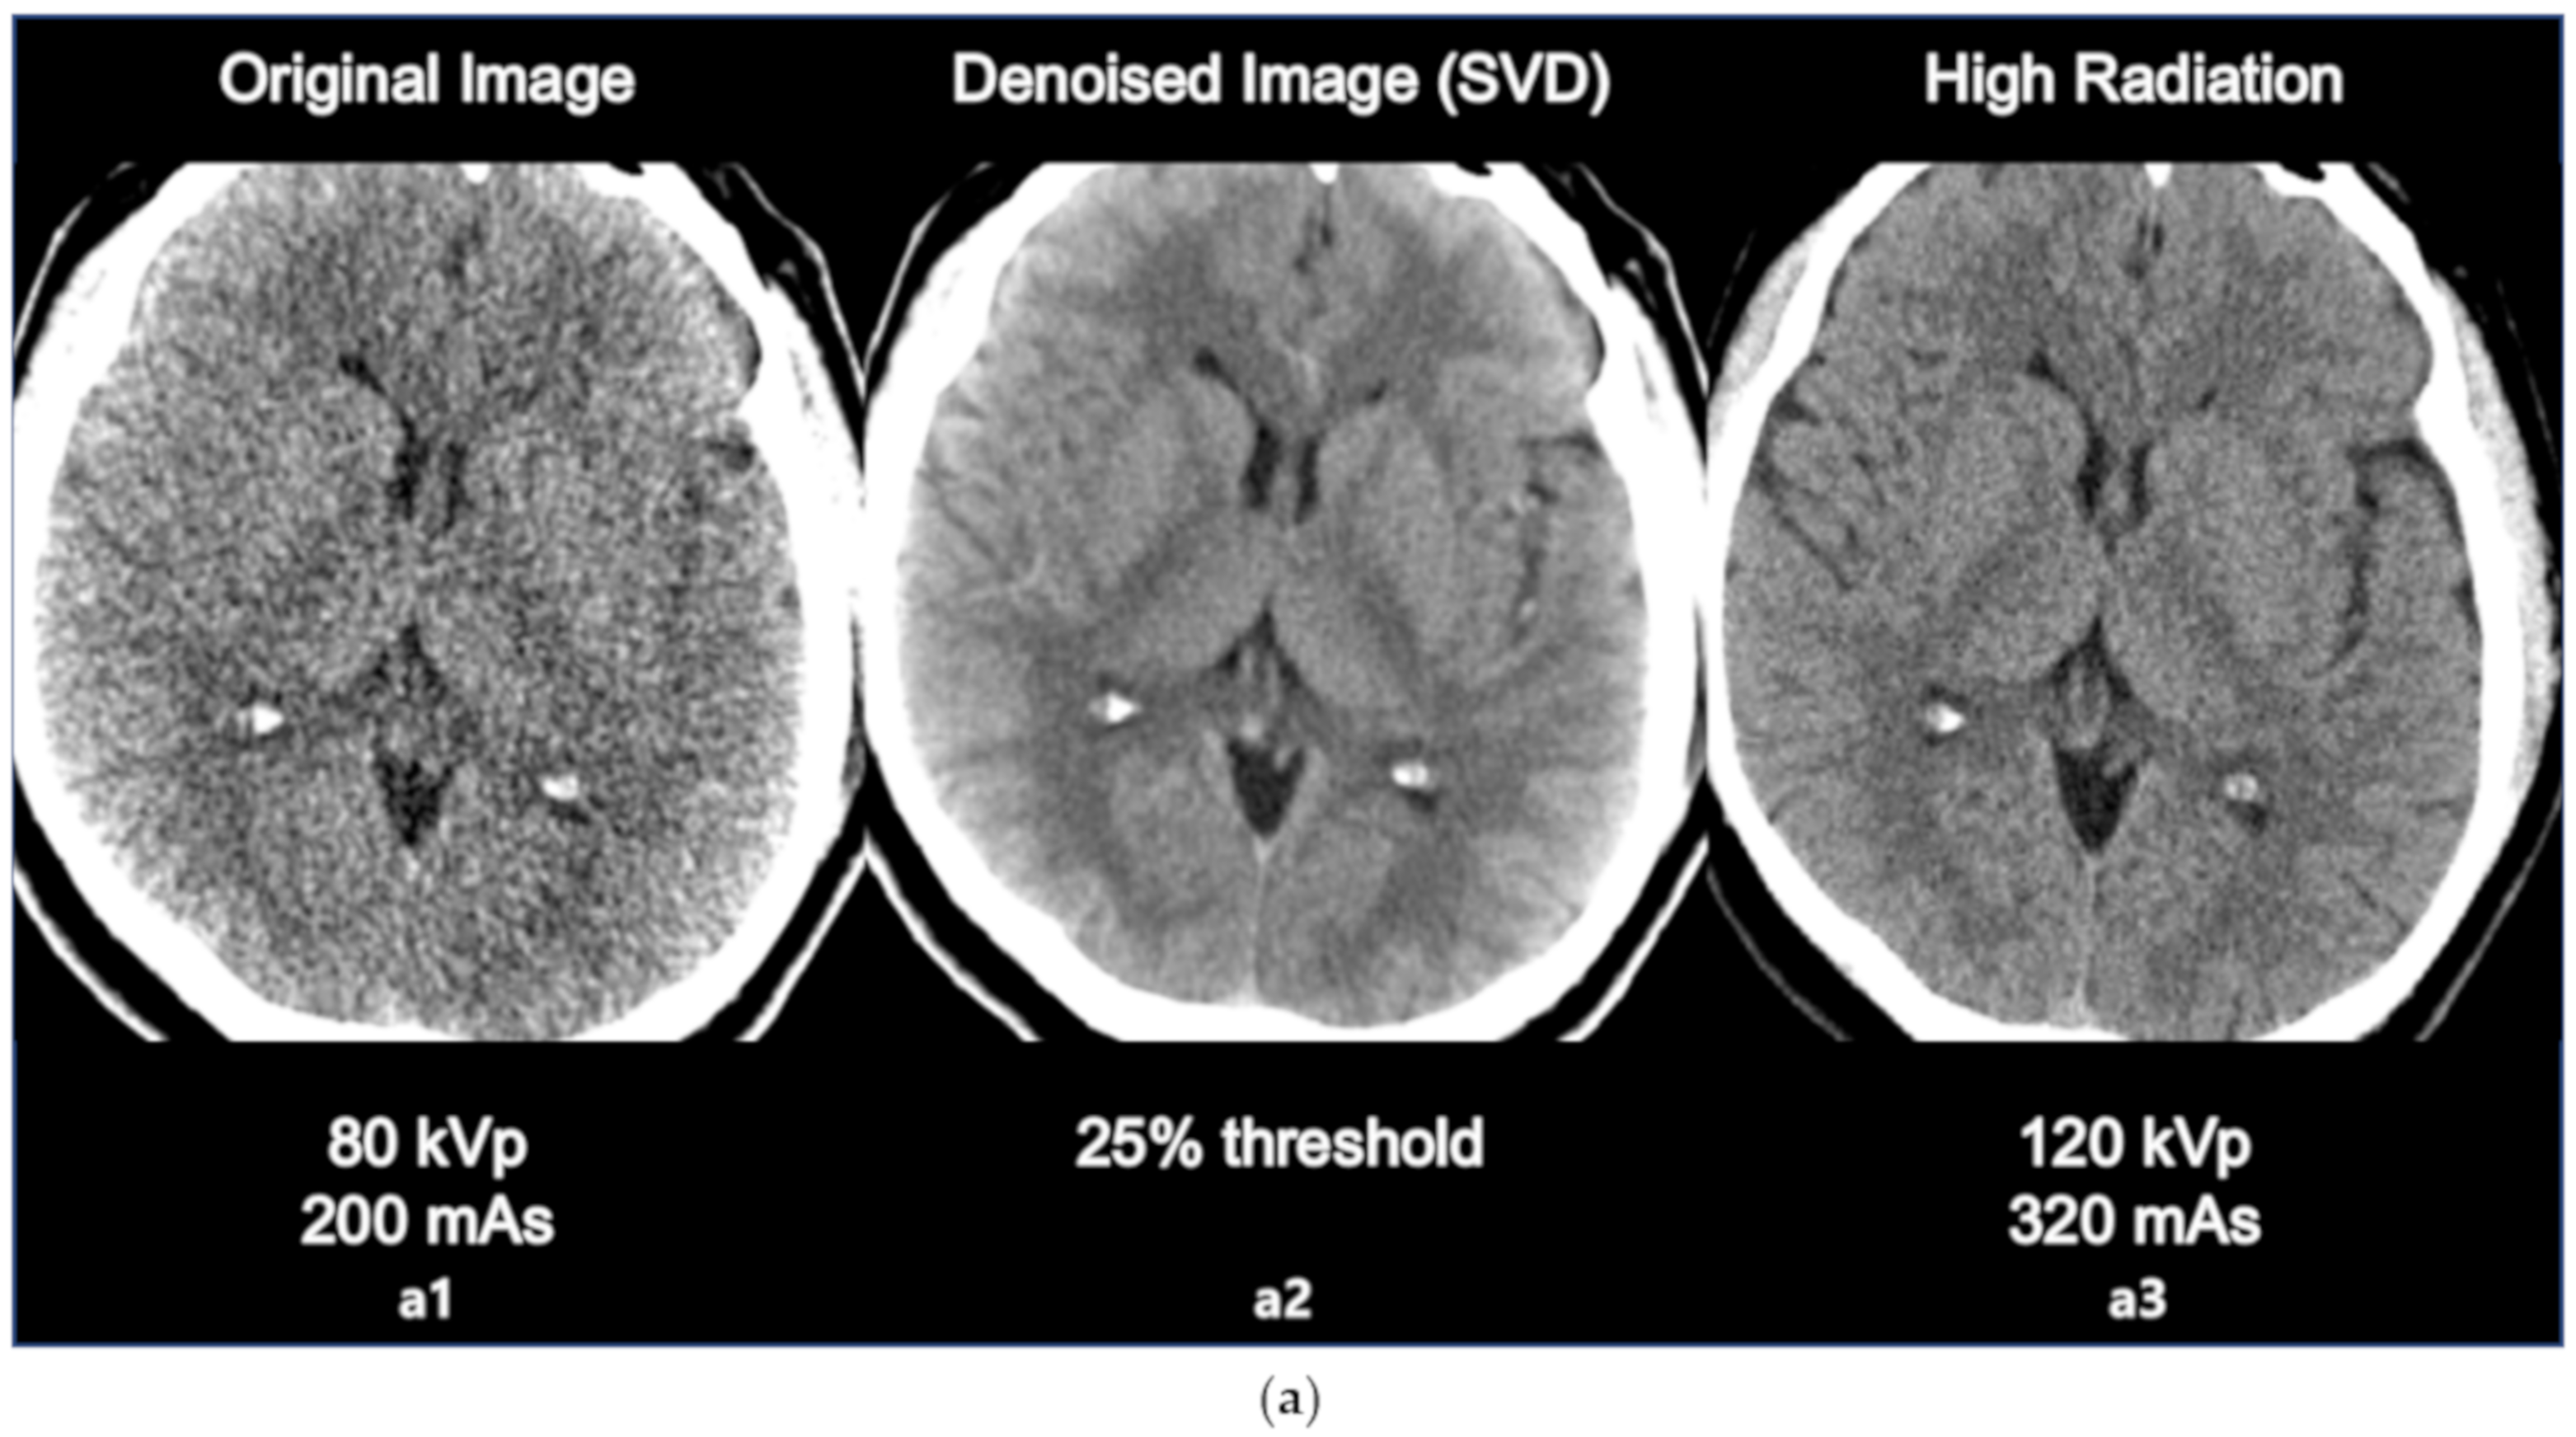

3.2. Comparison with High Radiation Dose Image

The comparison between original image, denoised image, and high radiation dose image is as in the following Figure 4a,b. The sharpness of ventricle and parenchyma margin, the distinctness of basal ganglia and parenchyma in the denoised image, and the differentiation of gray matter and white matter in the denoised image was clearly described close to original high dose image.

Figure 4.

(a) Comparison between the original image (80 kVp, 200 mAs, a1 the denoised image using SVD (25% threshold, a2, and the high dose image (120 kVp, 320 mAs, a3). (b) Comparison between the original image (80 kVp, 200 mAs, b1), the denoised image using SVD (25% threshold, b2), and the high dose image (120 kVp, 320 mAs, b3).

The results of the SNR and CNR estimations are presented in Figure 5a,b. In Figure 5a, the mean SNRs at the basal ganglia level exhibited a significant increasing tendency except for the 15% and 30% threshold values. The largest improvement involving a significant 16% increase (t = 2.908, p < 0.005) was observed at the 40% threshold setting. Similarly, in Figure 5b, the mean CNRs at the basal ganglia level maintained an increasing tendency for every threshold setting. The largest improvement involving a significant 43% increase (t = 6.327, p < 0.001) was also observed at the 40% threshold setting. However, image a6 that is labeled as 25% of the threshold value resulted in the best statistical significance per the results of the paired t test (t = 3.764, p < 0.001), resulting in an adequate 14% increase in the SNR. Considering the example dataset presented in Figure 3a, even though the 40% setting resulted in the highest SNR, the 25% setting appeared to generate more diagnostic information associated with the vessels. The 25% setting also resulted in good CNR estimation results with a statistically significant 37% increase (t = 6.080, p < 0.001). Based on these findings, we considered that the 25% setting could potentially be the optimal setting for 4D axial CTP images at the basal ganglia level in terms of compromising between noise reduction and preserving diagnostic information. In addition, we would like to highlight that we were able to achieve a considerable improvement in quantitative image quality in the denoised images without having to increase the radiation dose. Figure 4a,b shows the comparison of the original image with the lower dose image (80 kVp, 200 mAs, a1), the denoised image (80 kVp, 200 mAs, 25% of threshold, a2), and the higher dose image (120 kVp, 320 mAs, a3). Regarding Figure 4a,b, we would like to believe that we were able to improve the diagnostic value of low dose (Figure 4a,b, a2, b2) image similar to the ones scanned with high dose (Figure 4a,b, a3, b3) by using the proposed SVD-denoising technique. In other words, there is potential to preserve sufficient image quality even in scans involving lower tube currents. Lowering the tube current and tube voltage is the simplest way to reduce the radiation dose involved in a CT scan. Based on the fact that the amount of noise on an image is inversely proportional to the square root of the radiation dose, reducing tube current and tube voltage can inevitably lead to the degradation of image quality, thereby generating a larger amount of noise on the image [30,31]. Considering this, additional studies to investigate the qualitative and quantitative comparison between the denoised lower dose image and higher dose image on CTP may be meaningful. Additionally, further study with artificial biological objects using 3D bioprinting will be required for more accurate evaluation.